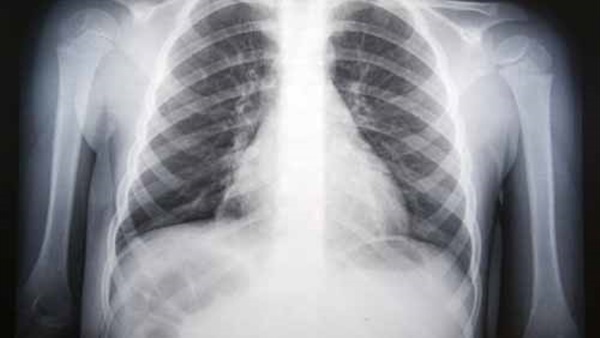

وكالات- الاقتصادي: قالت الرابطة الألمانية لأطباء الجهاز التنفسي إن الالتهاب الرئوي البكتيري يصيب الرئة بسبب بكتيريا المكورات الرئوية، التي تستوطن الجزء العلوي من الجهاز التنفسي، وتنتقل من المصاب بالرذاذ أثناء العطس أو السعال.

وأوضحت الرابطة أن أعراضه السعال المصحوب ببلغم، وسرعة وضيق التنفس، وسرعة ضربات القلب، والحمى، والارتعاش، والشعور العام بالإعياء والضعف.

وأضافت الرابطة أنه يعالج بالمضادات الحيوية، مشيرة إلى الوقاية منه بالتطعيم ضد بكتيريا المكورات الرئوية، الأمر الذي يعد مهماً بصفة خاصة للأكثر عرضة بالإصابة به، مثل كبار السن، وأصحاب الأمراض المزمنة، حيث قد يتخذ الالتهاب لديهم مساراً شديداً يهدد حياتهم.